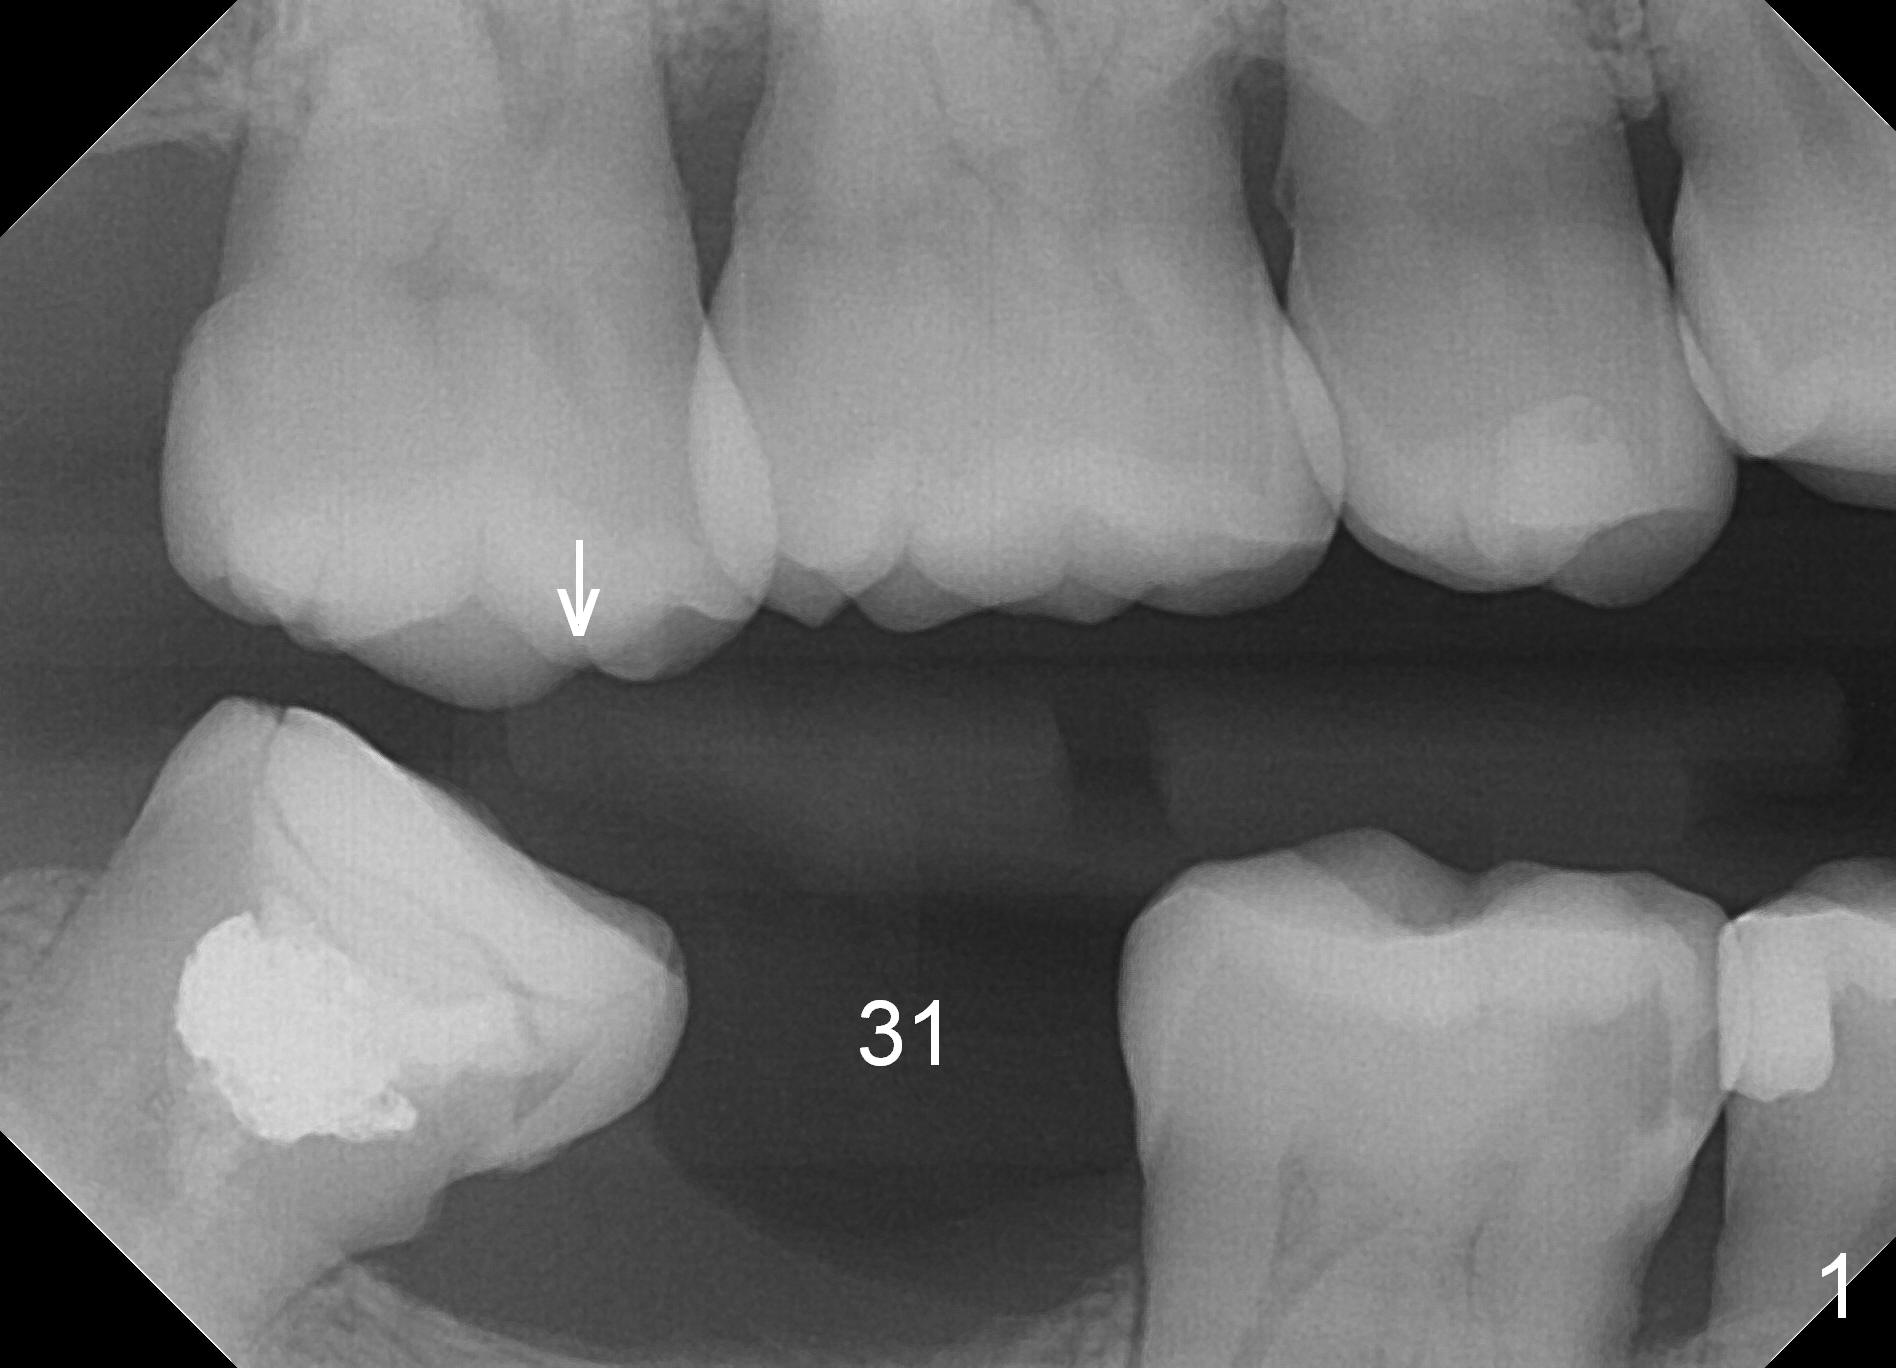

Narrow Mesiodistal Space M

A 39-year-old man presents to office for #19/20 composite redo. After discussion he agrees to restore #31 with implant (Fig.1-3). He worries about bone loss (buccolingually) because of 8-year loss of the tooth. Fortunately the mesiodistal space is less than 8 mm (Fig.3). A 4 mm IBS implant (Titanium V (Bicon as well) stronger (not easily break) than Titatium IV (Tatum, DIO)) should be able to sustain mastication if the tooth #32 is not extracted. After local anesthesia, remove calculus in the mesial surface of #32 (Fig.2 ^). Also prepare for MO composite at #30.